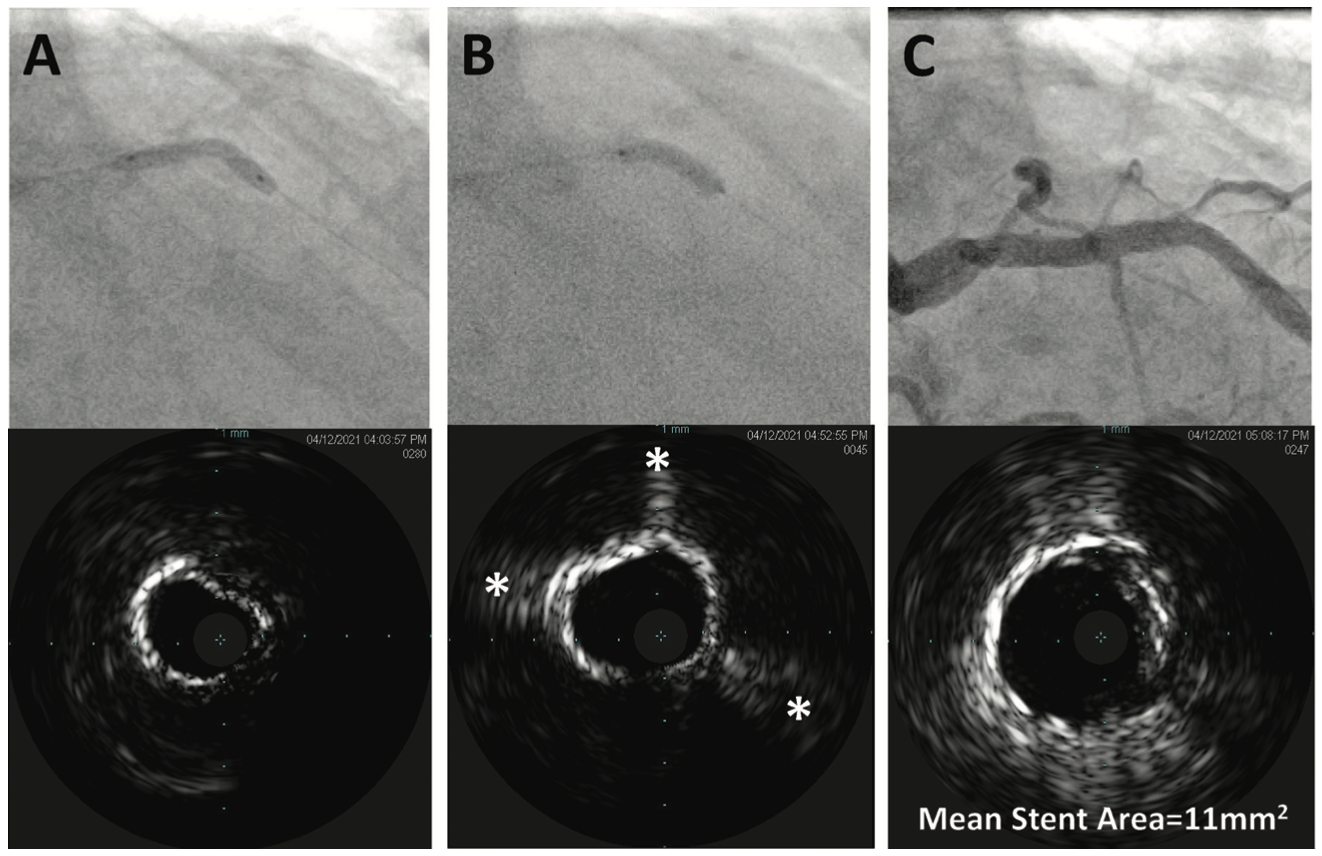

Before we were totally comfortable with this concept, we would always image after IVL use, looking for cracks in the arcs of calcium. If you can get the IVL catheter into a lesion, then you should then be able to get an imaging catheter into the lesion. With optical coherence tomography (OCT), the challenge is that it doesn’t see very deeply in the artery (often the calcium micro-fractures are too deep in the arterial wall to be seen with OCT), so you can’t always tell where there are cracks. I think it is easier to use intravascular ultrasound (IVUS). Although IVUS can’t see through calcium, cracks will appear as little rays of light extending into the deep layers of the artery, making it into areas that used to be dark shadow (see Figure). These are a good indication. In the beginning, visualizing these cracks can be subtle and a little intimidating, and this is where a one-to-one noncompliant balloon and doing the C-arm swing is helpful, especially when you are not confident about what you are seeing on imaging. If a noncompliant balloon that used to have a waist in it, now inflates with no waist, then you can feel comfortable that your stent is going to expand as well. If we see any sort of a waist in the noncompliant balloon, or if we image and don’t see that the calcium has been cracked, then our workflow involves, typically, going back in with either a cutting balloon or IVL, or rarely, atherectomy, if it is a focal area.